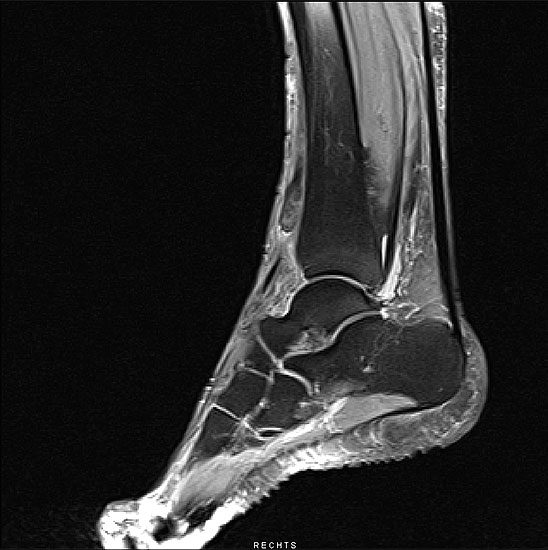

Bildgebende Diagnostik bei der Ruptur des MTA mittel MRT:

Sagitaler Schnitt  mit Darstellung des nach proximal retrahierten Stumpfes der rupturierten Sehne.

Abbildung 2

Der Gold-Standard zur Diagnostik einer ansatznahen Tendopathie des M. tibialis anterior ist die Magnetresonanz-Tomographie (Abbildung 2).

Hierbei können zum Beispiel  peritendinöse Flüssigkeitsansammlungen auf Höhe des Sehnenansatzes bzw. der distalen Anteile der Sehne darstellt werden. In Einzelfällen können Längsrupturen als Zeichen einer chronischen Schädigung nachgewiesen werden. Einschränkend ist zur Beurteilung der M. tibialis anterior-Sehne im MRT der anatomische Verlauf anzusehen. Schädigungen, insbesondere Längsrupturen, können aufgrund des Verlaufs außerhalb der MRT-Schichten leicht übersehen werden. Daher sollte die gesamte Sehne entsprechend ihres Verlaufes mittels Adaptation der Schnitteben erfasst werden. Das MRT stellt den Gold-Standard zur Diagnostik einer Ruptur der M. tibialis anterior-Sehne 1920 dar.

In der Regel tritt die Ruptur 0,5 bis 3 cm proximal der Insertion auf. Dieses Areal entspricht der anatomisch bekannten avaskulären Zone. Die Ruptur kann in der Regel auf den sagittalen und axialen Schnittbildern identifiziert werden. Bei Vorliegen des Verdachts auf eine M. tibialis anterior Sehnenruptur ist jedoch das zusätzliche Anfertigen schräg-axialer Flächen sinnvoll. Dabei sollte die schräg-axiale Schnittebene senkrecht zum Verlauf der M. tibialis anterior Sehne auf Höhe des anterioren Talus liegen mit einem Winkel von 45° zwischen der axialen und koronaren Fläche. Hierbei lassen sich insbesondere komplette Rupturen von partiellen Rupturen unterscheiden 21. Hinsichtlich der Gewichtung zeigen sich die Rupturen auf der T1-Schichtung mit Fettsättigung als auch auf der T2-Sequenz sehr gut. Meist lässt sich die Ruptur mit einem retrahierten Stumpf darstellen. Zusätzlich kann eine umgebende Signalerhöhung mit Erguss den Sehnenstumpf markieren (Abbildung 2).